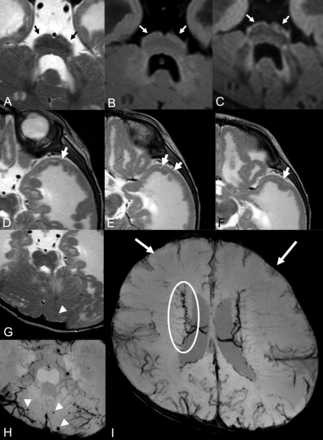

Brain MR imaging of patient 15. Brain stem images on T2WI (A), FLAIR (B), and DIR (C). There is a fluffy structure on T2WI (A, black arrows) and high intensity of the hypoplastic pontine surface on the FLAIR image (B, white arrows). High signal intensity along the brain stem surface on the DIR image is recognized more clearly than on the T2WI or FLAIR image (C, white arrows). T2WIs of the left temporal lobe (D–F) show lissencephalic and the abnormally located cortical superficial vessels running through the superficial layer of the lissencephalic cortex (white arrows). Microhemorrhages were seen in the cerebellar cyst on T2WI (G) and SWI (H). More microhemorrhages are recognizable on the SWI than on T2WI (white arrowheads). Cerebral SWI (I) shows hypoplasia of a superficial cerebral vein in both frontal lobes (white arrows) and dilated and tortuous subependymal veins (white circle).

The clinical and MR imaging findings for all 27 patients are summarized in the On-line Table. All patients showed brain stem hypoplasia (Figs 1 and 2). We observed a fluffy brain stem surface and mild high signal intensity along the surface of a hypoplastic pons on T2WI in 26 patients (96.3%) and FLAIR images in 25 patients (92.6%) (Figs 1A, -B and 2A, -B). The DIR images of all 6 patients showed high signal intensity along the brain stem surface (Fig 1C), and the high signal intensity was recognized more clearly on the DIR images than on the T2WI and FLAIR images.

Abnormally located superficial vessels beneath the cortex were observed in 3 patients (11.1%). The vessels ran through, inside, or beneath the lissencephalic cortex, and they were recognizable especially in the temporal lobes (Figs 1D–F and 2C–E). Hypoplasia of superficial cerebral veins around the frontal lobes was noted in all 5 patients who had SWI findings (Figs 1I and 3C, -D). Dilated and tortuous subependymal veins were identified in 2 of these 5 patients (40.0%) on SWI (Figs 1I and 3C, -D).

Hemorrhages were detected on T2WI in 3 of the 27 patients (11.1%) and on SWI in 3 of the 5 patients (60.0%). Patient 7 showed microhemorrhages in the cerebral and cerebellar cysts on SWI. Numerous microhemorrhages were seen in the cerebellar cysts in patient 15 on T2WI and SWI (Fig 1G, -H). Patient 23 exhibited a hemorrhage in the white matter around the occipital horn of the left lateral ventricle on T2WI and SWI. Patient 25 showed a hemorrhage in the white matter of the frontal lobe on T2WI (Fig 4).